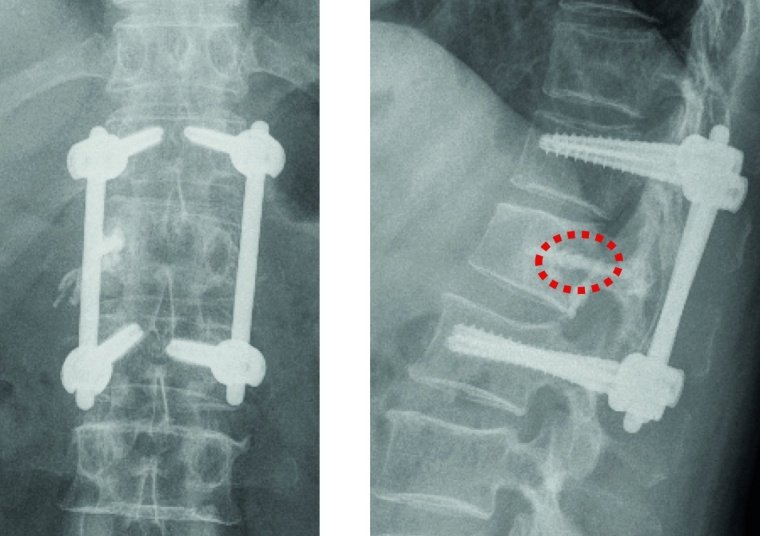

Fixateur interne: Haben die Osteolysen bereits Frakturen verursacht und weisen die betroffenen Wirbelkörper relevante Deformitäten auf, hat sich die perkutane überbrückende Stabilisierung mittels Fixateur interne bewährt (Abb. 2a und b). Der betroffene Wirbel kann ggf. additiv kyphoplastiert werden. Angesichts der sich zumeist anschließenden Radiatio verzichten wir jedoch zumeist darauf. Die Schrauben können je nach Knochenqualität zur Erhöhung der Stabilität wie üblich auch zementaugmentiert werden.